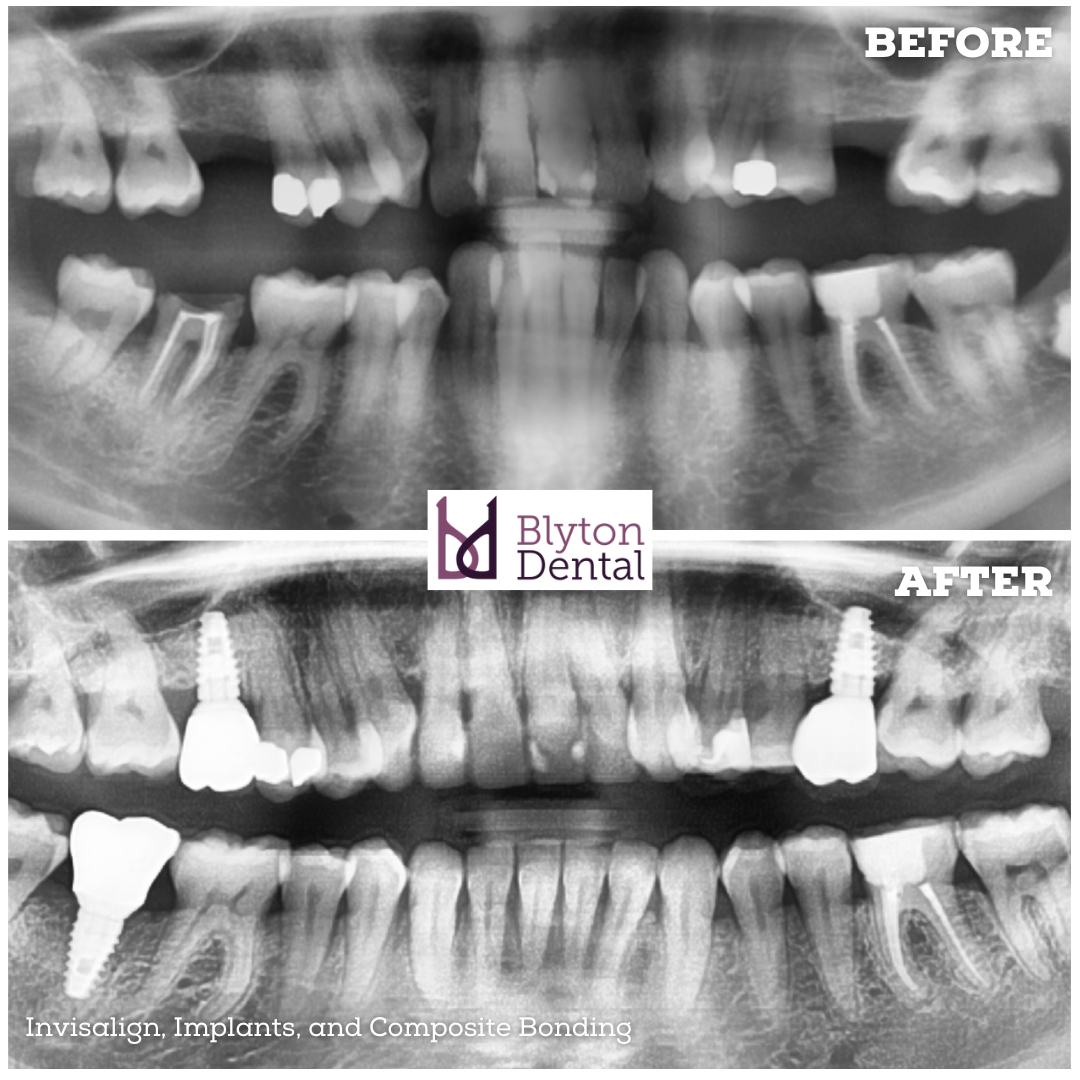

This lady was unhappy with the appearance of her teeth.

She had a couple of missing teeth, as well as a broken molar at the back.

After a full assessment, we discussed a combined approach to restore both the function and appearance of her smile.

Her teeth were first straightened with Invisalign, creating a more even and harmonious alignment.

We placed dental implants to replace the missing teeth at the beginning of the Invisalign treatment.

As soon as the teeth were straight, we restored the implants with crowns...

And finally, we refined her smile with composite bonding to perfect the overall aesthetics.

The transformation has been fantastic and as you can see, the results speak for themselves.